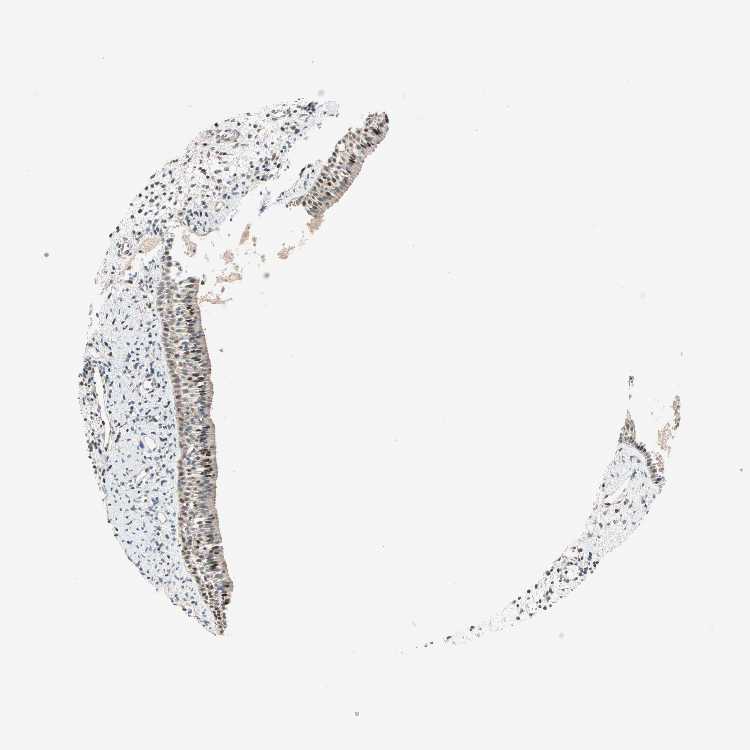

TISSUE PRIMARY DATA NASOPHARYNX Show tissue menu

NASOPHARYNX - Antibody stainingi

Antibody staining in the annotated cell types in the current human tissue is reported as not detected, low, medium, or high, based on conventional immunohistochemistry profiling in selected tissues. This score is based on the combination of the staining intensity and fraction of stained cells.

Each image is clickable and will lead to virtual microscopy that enables deeper exploration of all samples and also displays staining intensity scores, fraction scores and subcellular localization as well as patient and tissue information for each sample.

Antibody HPA007593Antibody HPA007609

Respiratory epithelial cells HighMedium